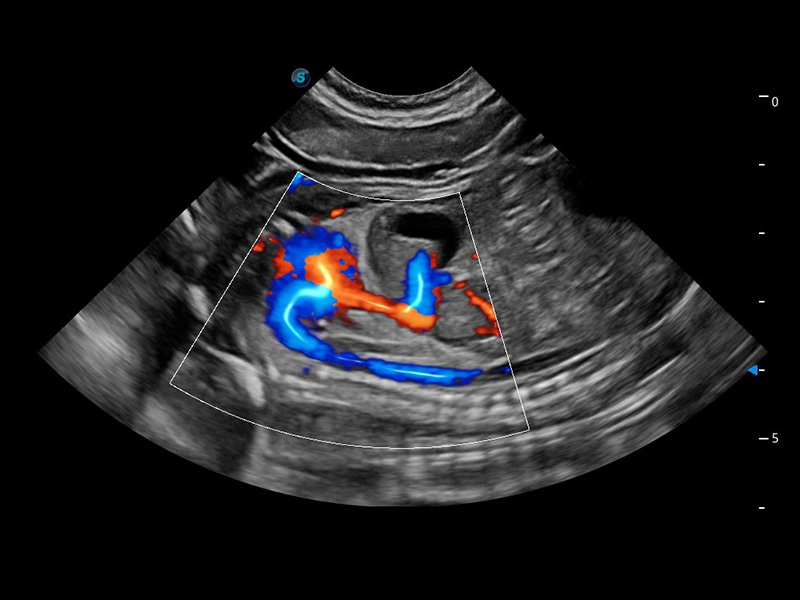

ProPet 60 作为一款高端台式动物超声设备,为动物医生的日常诊断提供了一系列贴合动物临床需求、解决临床实际问题的高级成像功能。凭借全系列高清探头,满足医生对腹部、心脏、生殖、浅表、肌骨等成像的所有需求,切实帮助您提升检查效率,提高诊断信心。

兽用彩色多普勒超声诊断系统

动物是人类最亲密的朋友和最值得信赖的伙伴。新葡的京集团8814检测站也一直致力于探索动物专用的超声影像解决方案。 全新推出的ProPet系列,是新葡的京集团8814检测站在动物超声影像智能化、专业化、精准化的一次跨越式革新。动物不能用言语来表述自己的不适,通过超声影像,ProPet系列搭建了动物医生与不同物种沟通的“桥梁”,为动物医生注入了“治愈之力”。